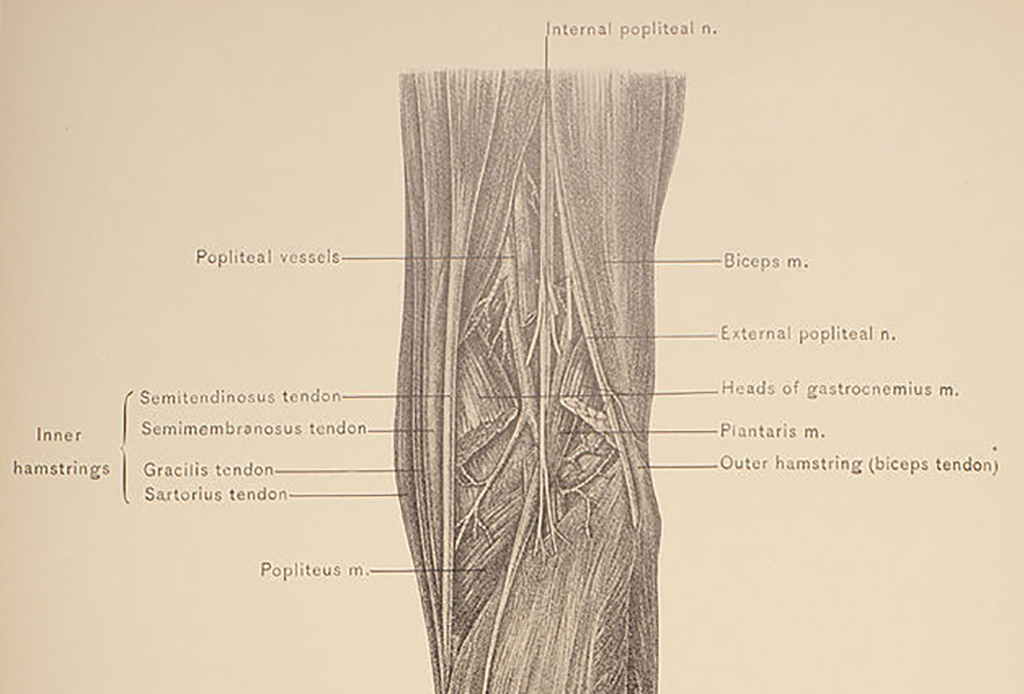

A Pointless Leg Muscle

Around nine percent of the human population has a completely useless muscle in their leg. It's what's known as the Plantaris muscle and actually did have a purpose back when humans resembled monkeys more so than a person.

It helped us to grip and manipulate objects with our toes, but we eventually stopped having a need for it thanks to our fingers, and especially our thumbs! The Plantaris muscle is actually so useless that surgeons take from it when reconstructing other parts of the body during surgery.